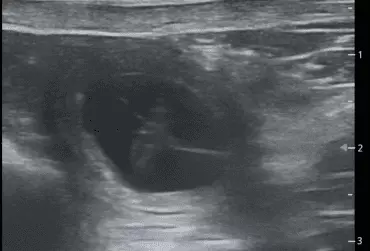

W literaturze opisano niewiele przypadków ciąż bliźniaczych jednokosmówkowych u suk. W trakcie wczesnej diagnostyki ultrasonograficznej ciąży u suki rasy whippet (chart angielski) zobrazowano pęcherz ciążowy, w którym znajdowały się dwa zarodki. Podczas badań kontrol­nych zarodki, a później płody wykazywały prawidłową organogenezę i żywotność. Ich rozwój przebiegał podobnie względem pozostałych ośmiu płodów. W 63. dniu ciąży wykonano zabieg cesarskiego cięcia i wydobyto dwa płody tej samej płci, o bardzo podobnym wyglądzie, z dwóch pęcherzy płodowych przyczepionych do jednego łożyska, oraz pozostałe osiem płodów.